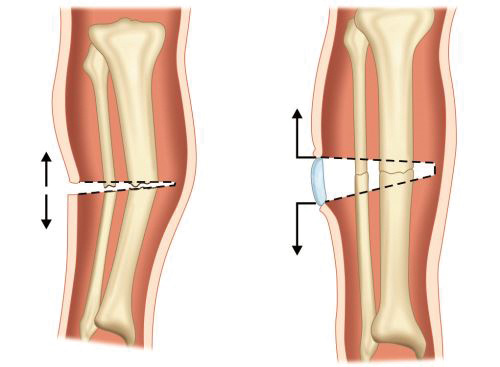

-

Inadequate reduction (Fig. 1.16)

-